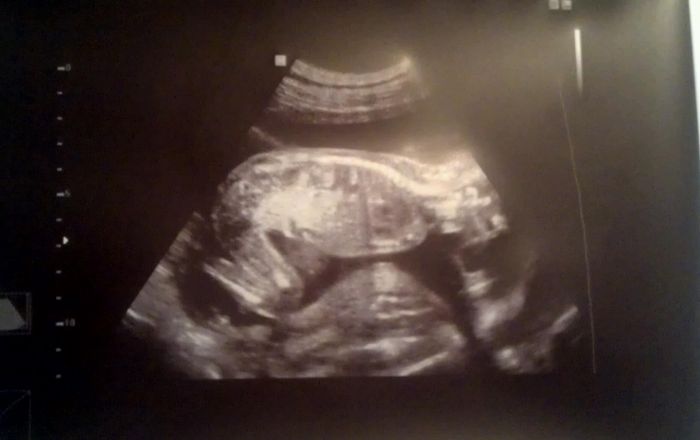

Ahoj holky, přikládám foto z minulého týdne :) utz ve 21+2, malá hodně zlobila takže se nám moc fotek nepodařilo, ale aspoň něco :) jinak je naprosto v pořádku a akční, oblíbená poloha na bříšku s kolinkama pod sebou:) všem přeji pohodove tehulkovani a jen dobre zpravicky :) hezkou středu, papa